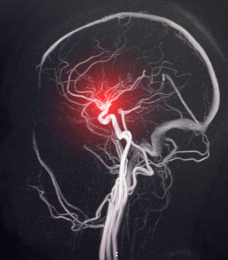

뇌출혈을 확인하기 위해 이미지 검사가 수행됩니다. 이러한 검사에는 다음이 포함될 수 있습니다

- CT 스캔 (Computed Tomography) : 뇌 출혈을 식별하기 위한 일반적인 검사입니다. CT 스캔은 출혈의 위치, 크기 및 심각성을 평가하는 데 사용됩니다.

- MRI (Magnetic Resonance Imaging) : 출혈의 정확한 위치와 크기를 확인하는 데 도움이 될 수 있습니다.

- 뇌혈관 조영술 (Cerebral Angiography) : 혈관의 이상을 확인하고 동맥류 등의 혈관 이상을 확인하는 데 사용될 수 있습니다.